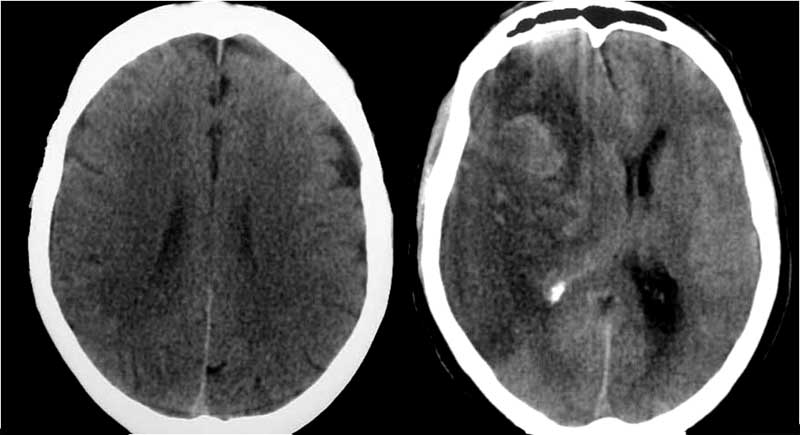

SIGNO DE LA ARTERIA CEREBRAL POSTERIOR HIPERDENSA

A la izquierda, hiperdensidad de ambas arterias cerebrales posteriores flechas). A la derecha, estudio a las 24 horas con infartos de los territorios de ambas cerebrales posteriores.

Es un signo precoz de infarto por obstrucción por trombo o émbolo que afecta a la circulación posterior cerebral. El significado de la imagen es el mismo que el de la arteria cerebral media hiperdensa, más conocido y frecuente.